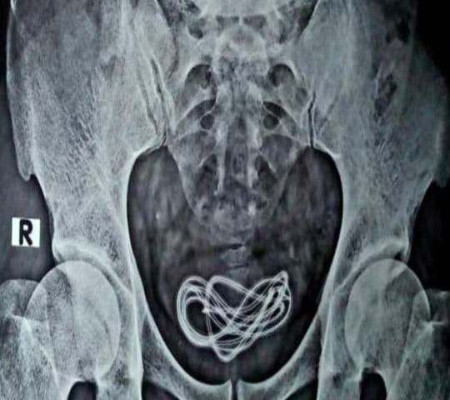

Um indiano precisou fazer uma cirurgia de urgência após a equipe médica realizar um raio-x e constatar a presença de um carregador de celular dentro do aparelho reprodutor do paciente.

Exame mostra o carregador no aparelho reprodutor do indiano. Crédito: divulgação.

Com fortes dores abdominais, ele disse aos médicos que havia engolido o carregador por engano, mas que não conseguia defecar o fio. No entanto, após uma cirurgia e os médicos não encontrarem nada no intestino, foram feitos novos exames que mostraram o fato.

O caso chocou todo o hospital. "Se ele tivesse sido honesto no início, dito que havia introduzido o carregador, ele nos teria poupado trabalho. Fiz uma incisão lá e puxei o cabo, que na verdade era um cabo de carregador com mais de 60 centímetros de comprimento. Ele veio aqui 5 dias depois do ocorrido", disse Walliul Islam, cirurgião geral do hospital que atendeu o homem.